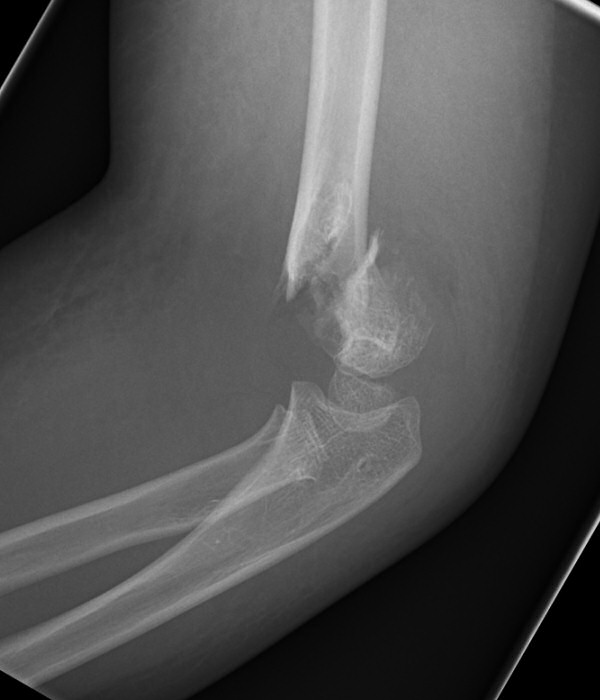

Suprakondylär humerusfraktur, Gartland 2, opererades med stiftning